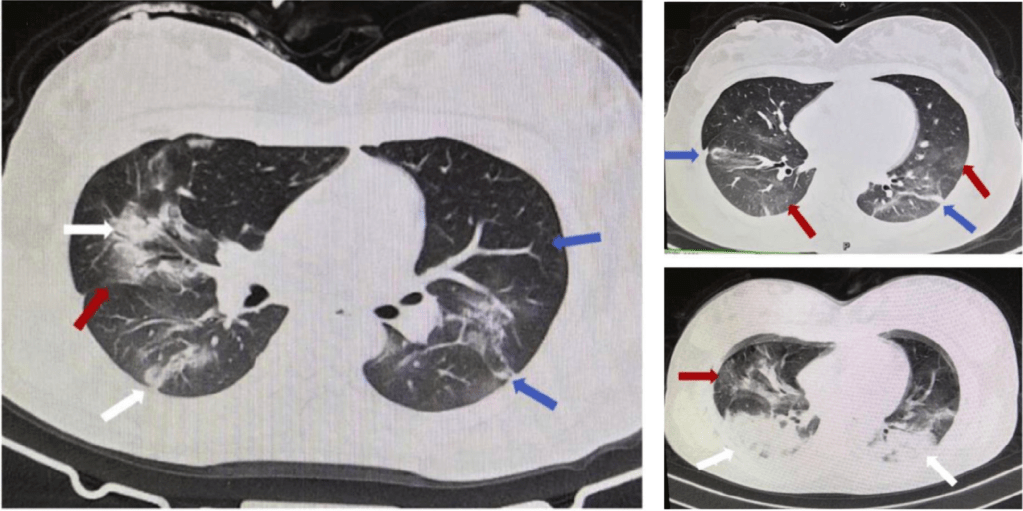

Hay muchas mujeres embarazadas que presentan la enfermedad por coronavirus 2019 (COVID-19), que sin duda amenaza la vida tanto de la madre como del bebé. Actualmente, no existen estadísticas sobre mujeres embarazadas infectadas con COVID-19. Una revisión retrospectiva ha indicado las características clínicas de nueve mujeres embarazadas con COVID-19. Sin embargo, se desconoce cómo se realizó la anestesia durante el parto. Aquí, presentamos un caso de anestesia espinal exitosa en una mujer con COVID-19 confirmado que requirió cesárea de emergencia. Cabe destacar que hubo 35 casos con COVID-19 confirmado que se sometieron a una cesárea de emergencia en el Hospital Wuhan Union desde el 23 de enero de 2020 hasta el 20 de febrero de 2020, con más investigación clínica en curso. [Ver artículo completo]